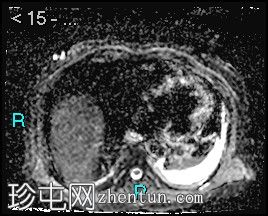

冠状位T2加权像

脂肪抑制像

胰腺钩突附近可见边界不清的肿块,T2加权像呈不均匀中等信号,弥散受限明显。肿块大小为4.1 x 5 x 3 cm(前后径 x 横径 x 头尾径)。伴有胰管扩张,直径约6 mm。

肝脏可见多个大小不一的可疑病灶(从亚厘米级到2厘米不等)。T2加权像呈高信号,弥散受限明显。

远端胆总管突然变窄,但未完全阻塞。

胰腺周围可见多发囊性病变,部分与主胰管相连,提示胰腺导管内乳头状黏液性肿瘤(IPMN)。

双侧胸腔积液,左侧较多。